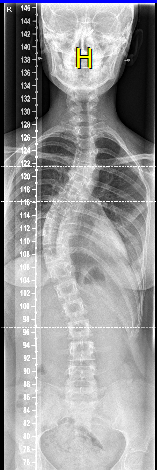

Die lag ook dezelfde dag nog op de ok. Anne. schreef:Dit ben ik! Enigszis bewerkt omdat de foto genomen is vanaf een computerscherm. Dat mijn schedel (links)boven donkerder is, is daar aan te wijten. Hetgeen waar het om gaat kun je duidelijk zien.. Zien jullie 't?

chanicha schreef:Scoliose s_v?